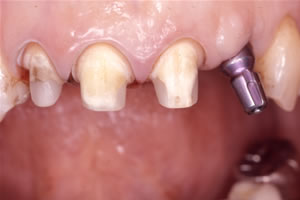

症例2![]() インプラント挿入後

![]() 印象時